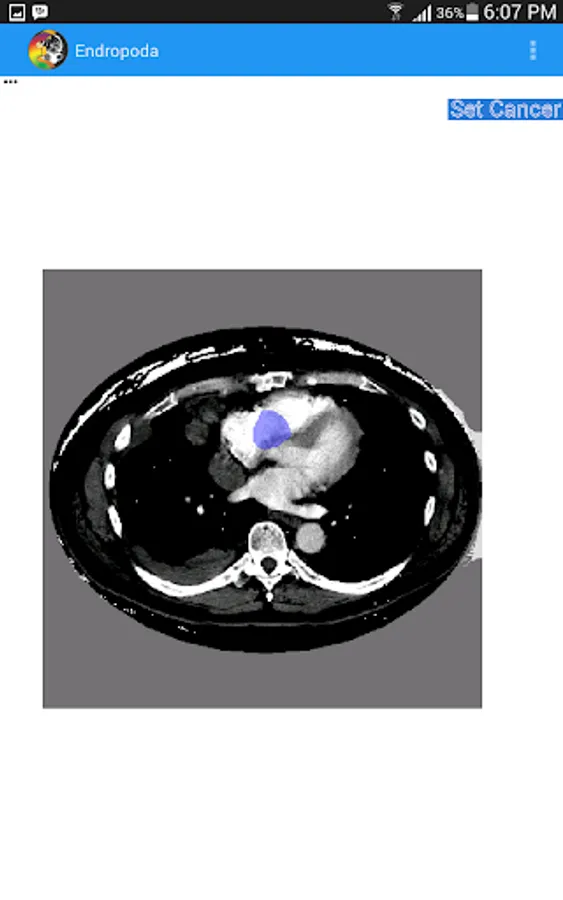

- Planning : In planning mode, user can create a region of interest on CT-Scan image to eliminate the background area and also can create cancer area that will be treated with radiation